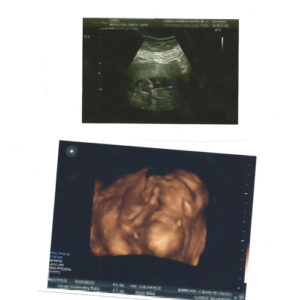

I’ve included a few Ultrasound pictures of our little Madison!